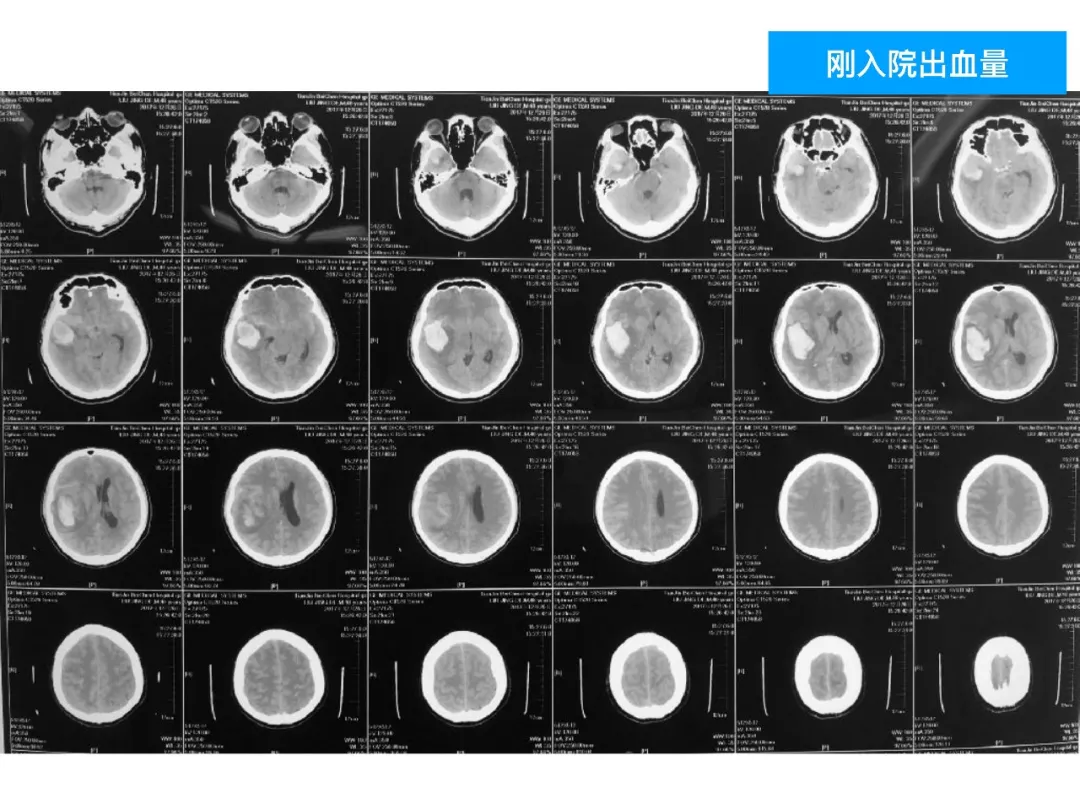

今天为大家分享的是《颅脑创伤-神经重症病例周刊》第四十九期,由天津市环湖医院神经外科五病区主任佟小光教授团队带来的:DAVF出血、脑疝急诊手术一例,欢迎阅读。

(1)DAVF引起如此严重的脑出血很少见,容易与普通脑出血混淆;